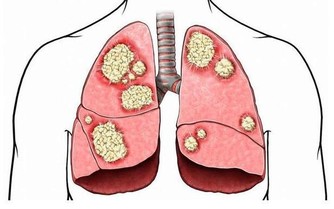

胃痛吃什麼食物好?8種食物別錯過

(1)小米粥。小米粥也是很養胃的。小米,有米黃金之稱,小米粥有暖胃和安神的作用。

(2)湯水。比較養胃的除了各種粥類外,還有湯湯水水,湯不能是肉湯,而是各種蔬菜湯,比如菠菜湯,雞蛋湯等等。

(3)牛奶。不僅僅含有大量的營養物質,還具有食療的效果,一般認為牛奶能夠治療陰虛胃痛、津虧便秘。

(4)主食。最能夠養胃的就是麵條,麵條比較軟,容易消化,對胃比較好,大米中含有過多的酸,所以不能過多的吃大米,如果熬粥的話,可以放少量小蘇打進去,粥比較容易熟爛,對胃比較好。

(5)綠葉青菜。綠葉青菜如菠菜,能夠增加食慾,有利於消化,含有的豐富的纖維素還能夠促進腸胃的蠕動,有利於排便,緩解胃部疼痛。

(6)南瓜。能夠補中益氣,消炎止痛。南瓜含有大量的果膠,可以吸附細菌以及有害物質,包括重金屬以及鉛等,所以南瓜具有排毒的作用,果膠還具有保護胃粘膜的作用,經常用南瓜熬粥能夠養胃。

(7)胡蘿蔔。具有小人參的稱呼,胡蘿蔔含有的胡蘿蔔素能夠轉化為維生素A,胡蘿蔔與肉一起燉,具有護肝養胃的療效。

(8)山藥。健脾胃、益腎氣,可促進消化吸收,也有保護胃粘膜的功效,還能促進食慾,胃部長期不適導致食慾不振的患者可多吃。老人養生可以多吃山藥,可以延年益壽。